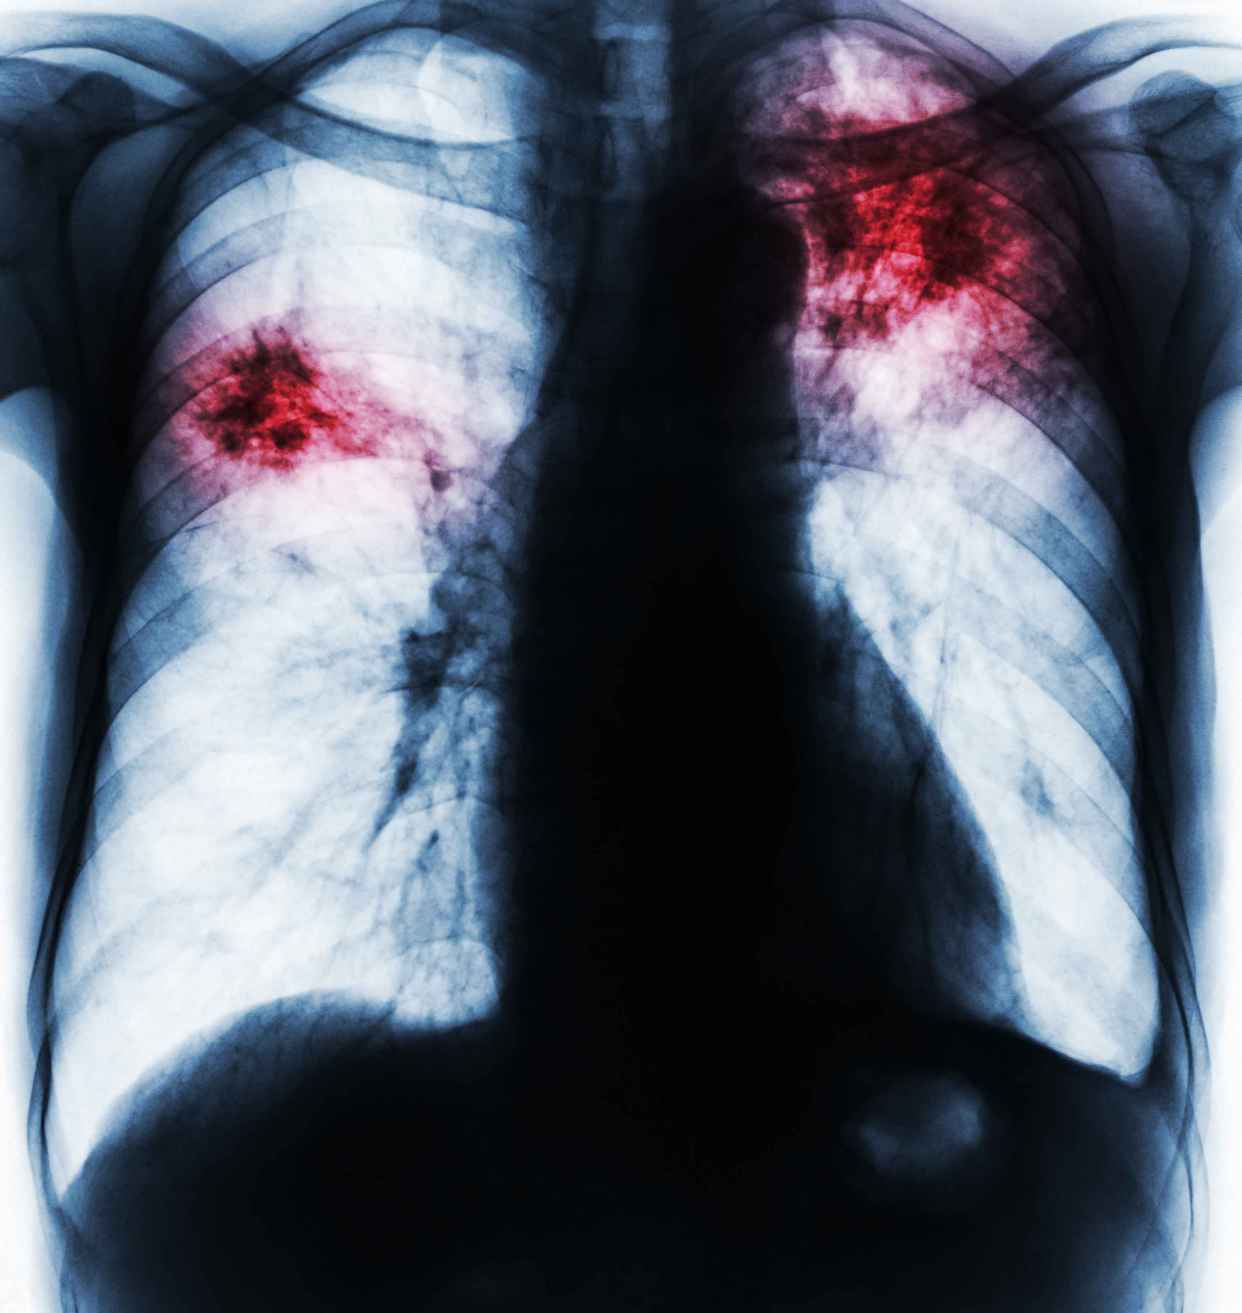

影像诊断中"肺纹理增多"该如何理解?

支气管扩张症 平片 两下肺纹理增 粗,模糊,集拢 和排列紊乱,可 见蜂窝